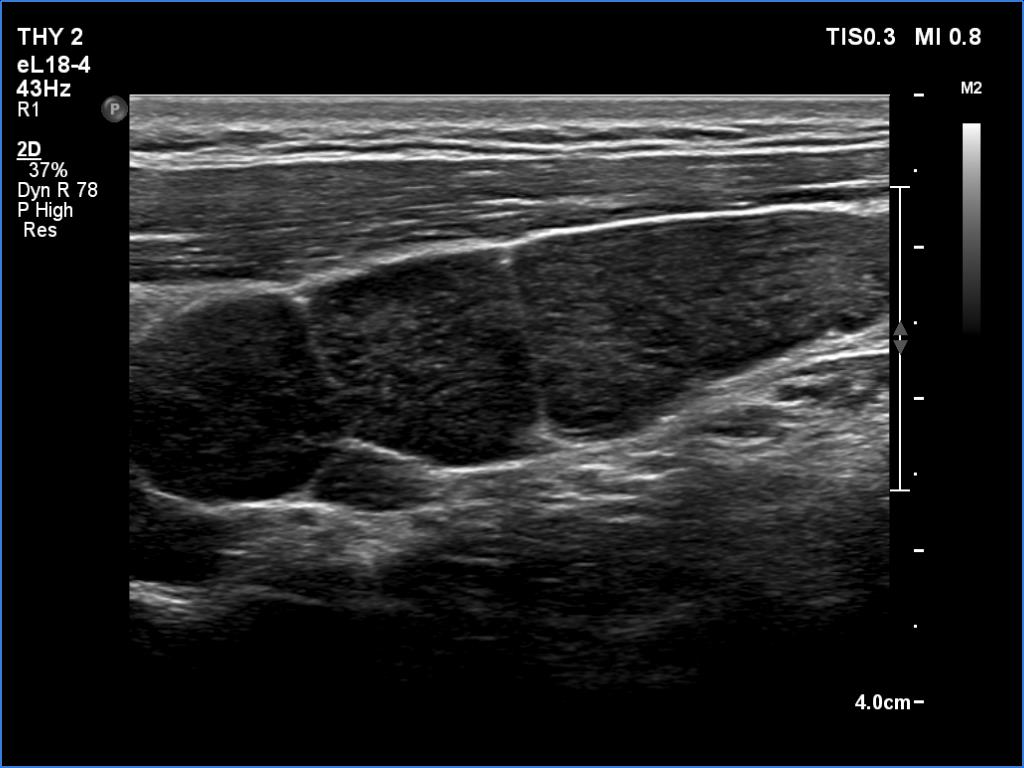

Ultrasonography. The thyroid was echonormal and had multiple minimally/moderately hypoechoic nodules. The lesion in the left lobe was remarkable due to lobulated margins. More than 10 lymph nodes larger than 1 cm in diameter were detected both in the right and the left side of the neck. Some had heterogenous pattern, most of them lacked regular hilum. The vascularity was varied from avascular to obviously irregular.